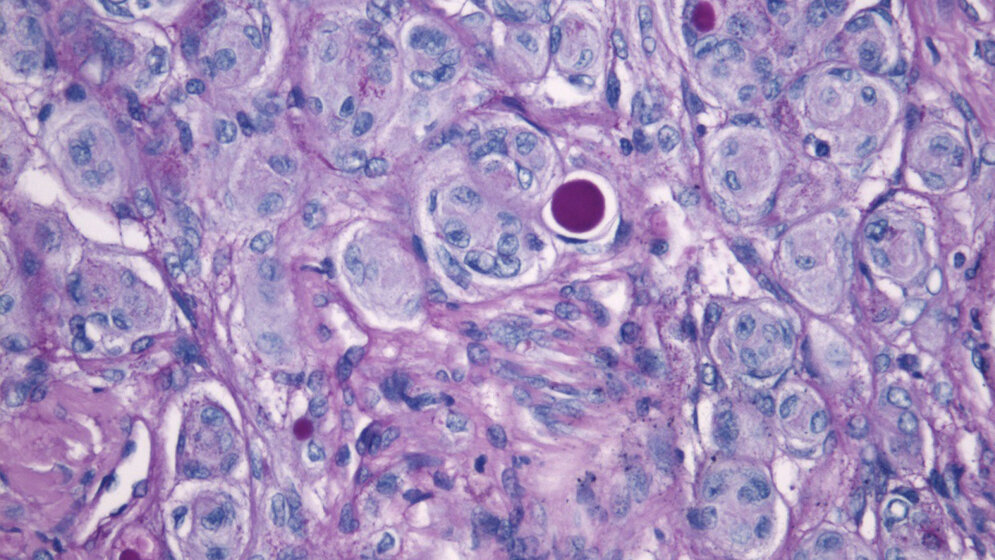

Die Folge ungenauer Klassifikationen sind vermeidbare Rückfälle bei zu harmlos eingestuften und daher fälschlicherweise nicht bestrahlten Tumoren oder unnötige Bestrahlungen im umgekehrten Fall. Die WHO-Einteilung beruht bislang auf dem Erscheinungsbild der Tumorzellen unter dem Mikroskop. Die Heidelberger Forschungsergebnisse tragen dazu bei, unter Berücksichtigung molekularer Marker die WHO-Einteilung zu überarbeiten und damit die Therapie von Hirntumorpatienten zu verbessern.

Meningeome sind die häufigsten Hirntumoren bei Erwachsenen. Sie entstehen aus der Hirnhaut und machen etwa ein Drittel aller Hirntumoren aus. Sie werden bislang anhand des Erscheinungsbildes ihrer Zellen gemäß WHO-Klassifikation in die Grade I bis III eingestuft, wobei rund 80 Prozent der Meningeome als gutartig gelten und dem Grad I zugeteilt werden. Die Patienten können durch eine vollständige operative Entfernung des Tumors in der Regel geheilt werden. Bei Grad II wird individuell entschieden, ob eine anschließende Strahlentherapie notwendig ist. Bei Grad III ist die Wahrscheinlichkeit für Rückfälle am größten, hier werden die meisten Patienten bestrahlt.